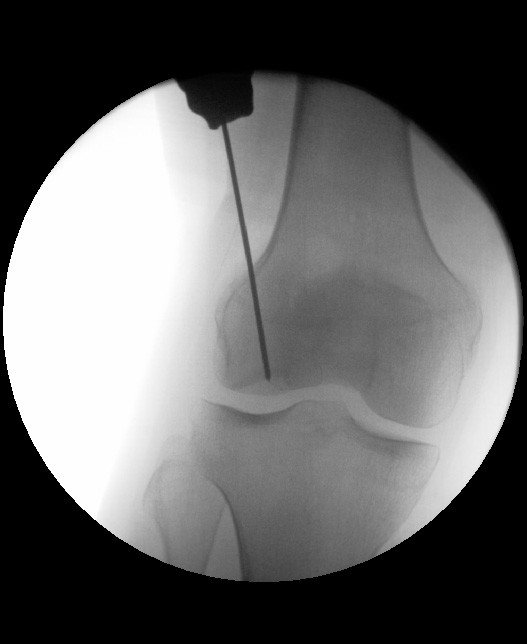

In frühen Stadien, bei welchen der Knochen nur leicht beschädigt und der überliegenden Knorpel sicher intakt ist, kann eine sogenannte retrograde Anbohrung durchgeführt werden. Dabei wird unter Zuhilfenahme eines Röntgengerätes der Knochen von hinten=retrograd (ohne die Knorpelschicht zu verletzen) unter Verwendung von beispielsweise Drähten angebohrt (Abbildung). Dadurch wird der defekte Knochen abgetragen und es gelangt zugleich frisches Blut in den Defektbereich. Aus diesem Blut kann sich dann neuer Knochen entwickeln. Hat sich das Knorpelknochenstück bereits teilweise gelöst, befindet sich aber mit intakter Knorpelschicht noch im Defektbereich kann das gesamte Stück nach Anfrischung oder Erneuerung des unterliegenden Knochens wieder eingesetzt werden und dort mit Schrauben fixiert werden. Die Schrauben werden dann im Verlauf wieder entfernt. Ist die Knorpeloberfläche bereits defekt und kann so nicht erhalten werden müssen die standardisierten Verfahren der Knorpeltherapie angewandt werden. Hierbei muss dann in der Regel immer auch der Knochen ersetzt werden, da dieser als Grundpathologie des gesamten Geschehens anzusehen ist.